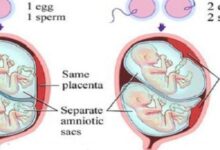

- الأسبوع الثاني: يحدث التبويض (بالإنجليزية: Ovulation) بداية هذا الأسبوع، وتُخصّب البويضة بعد تقريبًا 12-24 ساعة من قبل الحيوان المنوي، وبمجرّد تخصيبها تبدأ بالانقسام إلى خلايا متعددة من خلال سلسلةٍ من العمليات المعقدة، ويكون ذلك أثناء انتقالها إلى أسفل قناة فالوب، ثمّ تدخل الرحم وتبدأ بالانغراس في بطانته.[٣]

- الأسبوع الثالث: وفيه تنزرع أو تنغرس البويضة المخصبة في بطانة الرحم الغنية بالمواد الغذائية، وتسمّى حينئذٍ الكيسة الأريمية أو الكبسولة البلاستوليّة (بالإنجليزيّة: Blastocyst)، إذ تكون ككرة صغيرة جدًا تتكون من مئات الخلايا التي تتكاثر بسرعة وتتطور إلى جنين، ولإيقاف المبيضين عن إطلاق المزيد من البويضات لاحقًا تُنتج هذه الخلايا هرمون الحمل (بالإنجليزية: Pregnancy hormone) المعروف علميًا بهرمون موجهة الغدد التناسلية الميشمائية البشرية واختصارًا hCG.[٣]

- الأسبوع الرابع: يكون الجنين الآن قد التصق بجدار الرحم، وتستمرّ الخلايا بالانقسام التي ستُكوّن أعضاؤه في الفترة القريبة، وقد يمكن رؤيته بالموجات فوق الصوتية لكن يكون بحجمٍ أصغر من حبة الأرز، ويبدأ هنا تشكّل الكيس الأمنيوسي أو ما يُعرف بكيس الحمل (بالإنجليزية: Amniotic sac) وهو أشبه ما يكون بوسادة مملوءة بسائل تحيط بالجنين وتحميه أثناء نموّه، ويكون الكيس متصلًا بالكيس المحّي أو الحويصلة السرية (بالإنجليزية: Yolk sac) ليُمدّ الجنين بالمواد الغذائية خلال الأسابيع الأولى.[٢]

- تتطوّر المشيمة (بالإنجليزية: Placenta) بما يكفي لتصبح مسؤولة عن نموه بعد ذلك، فستكون تقريبًا جاهزة لتوصيل العناصر الغذائية التي يحتاجها الجنين وإزالة الفضلات من جسمه، ويُشار أنّه حتى هذه المرحلة كان المبيضان هما المسؤولان عن إنتاج هرمون البروجسترون (بالإنجليزية: Progesterone) الضروري لنموه.